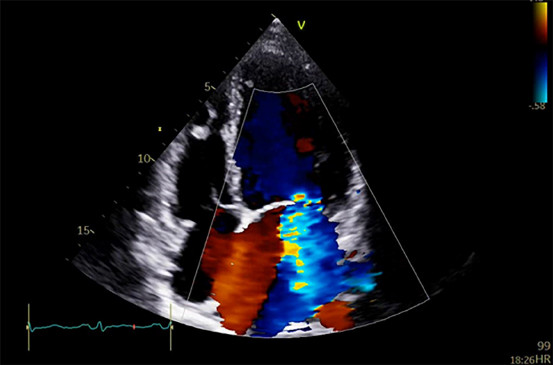

En la ecocardiografía se percibió dilatación y disfunción grave del ventrículo izquierdo (VI) con fracción de eyección del ventrículo izquierdo (FEVI) de 20 %, función del ventrículo derecho (VD) en el límite de la normalidad e insuficiencia mitral secundaria grave (Figura 2).

Fig. 2

Ecocardiografía transtorácica donde se observan dilatación grave del ventrículo izquierdo e insuficiencia mitral secundaria grave.